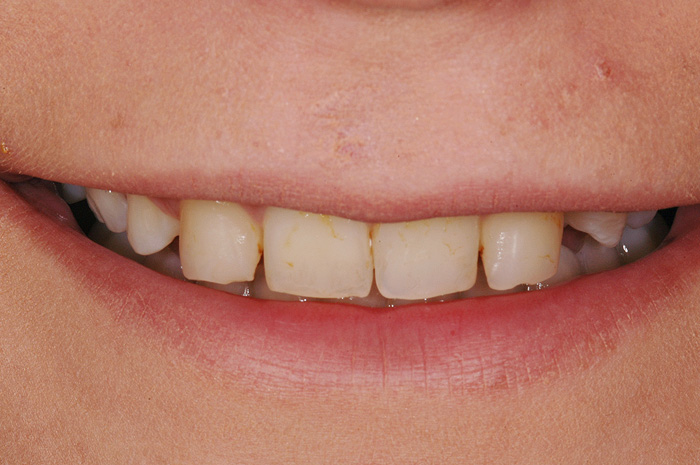

Ist ein Zahn sehr stark oder bis unter das Zahnfleisch zerstört, kann er nicht mehr mit einer herkömmlichen Kunststofffüllung versorgt werden. Der noch vorhandene Restzahn lässt sich nur noch durch eine Krone restaurieren. Sie besteht aus einem individuell gegossenen Metallgerüst, auf welches in mehreren Schichten Keramik aufgebrannt wird oder kann als rein vollkeramische Krone hergestellt werden, was zu einer noch höheren Ästhetik führt.

Die Restauration eines Zahnes mit einer Krone ist aufwendig. In einem ersten Schritt wird Karies und das alte Füllungsmaterial vollständig entfernt und der Zahnstumpf wieder aufgebaut. Eine präzise Abformung der Situation dient dem Zahntechniker als Grundlage für ein Gipsmodell, auf dem er die Krone herstellt. Sofern Farbe und Form perfekt stimmen, kann die Krone in einer zweiten oder dritten Sitzung beim Zahnarzt zementiert werden. Für die Zeit zwischen Präparation des Zahnes und dem definitiven Zementieren der Krone wird der Zahn mit einem individuell hergestellten Provisorium versorgt.